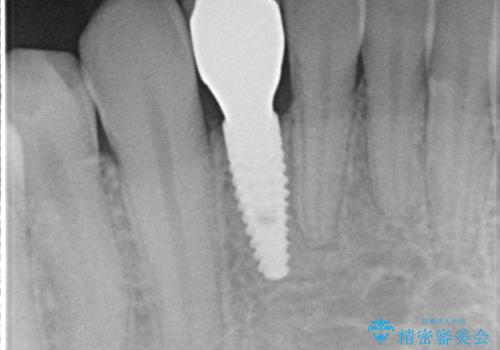

- 下の前歯が1本生まれつき少なかったため、インプラント治療を行いました。

インプラントの前に矯正治療を行い、入れる隙間を確保しました。

ブリッジにすることも可能でしたが、両側の歯が天然歯であること、また、事前に矯正で噛み合わせを整え、幅も確保していたこと、CTにより骨の厚みがある程度あったことを踏まえ、インプラントも可能であるとお話しし、選んでいただきました。

唇側の骨増成もしっかり行い、前歯部インプラントによくある、歯茎が下がって見えることもない、審美的なインプラント補綴ができました。